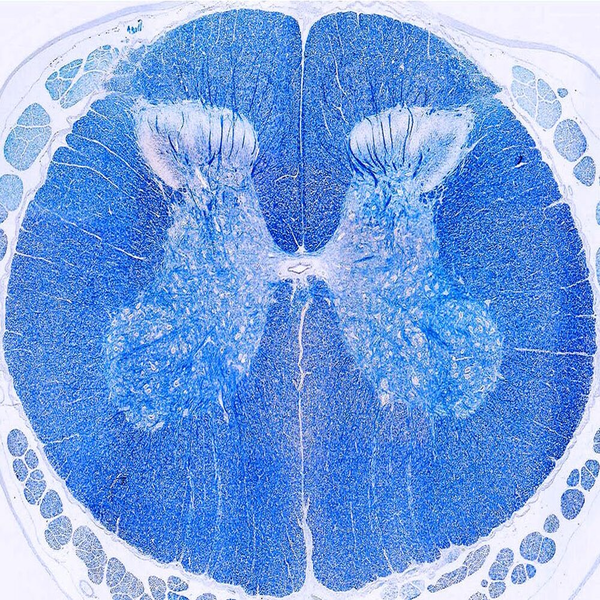

- General and specialized tissue and cell staining

- Prepare educational slides for students from all available tissues

Histological methods includes sample processing in the pathology laboratory, preparation of the slide and its examination under a microscope, sample fixation, molding, microtome cutting, staining and assembly of the slides.